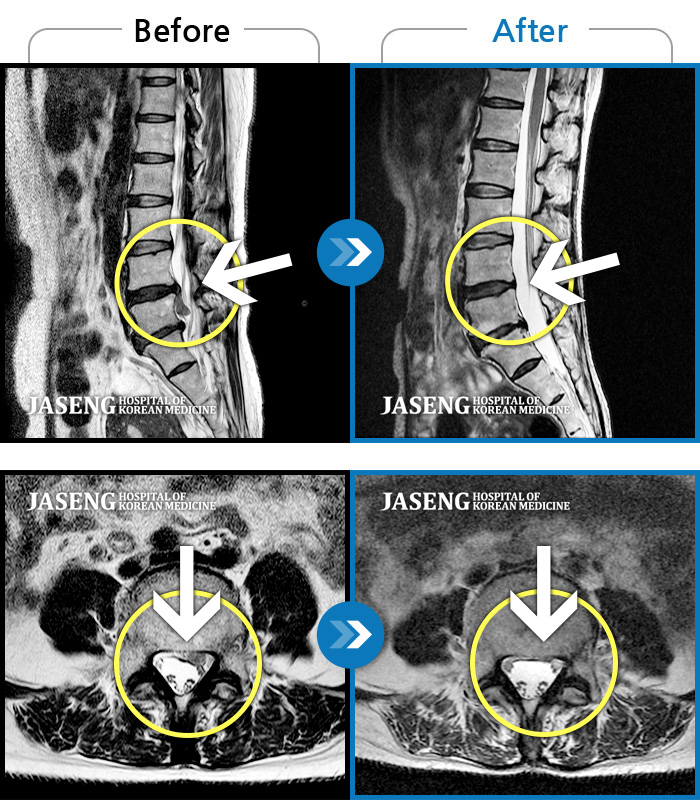

허리디스크

대전 · 김창연 원장

엉덩이의 왼쪽 부위 및 하지방사통이 심각하여 보행이 불가한 상태에서 내원하셨습니다.

촬영시기

2025.01.22 ~ 2025.08.09

2025.08.19